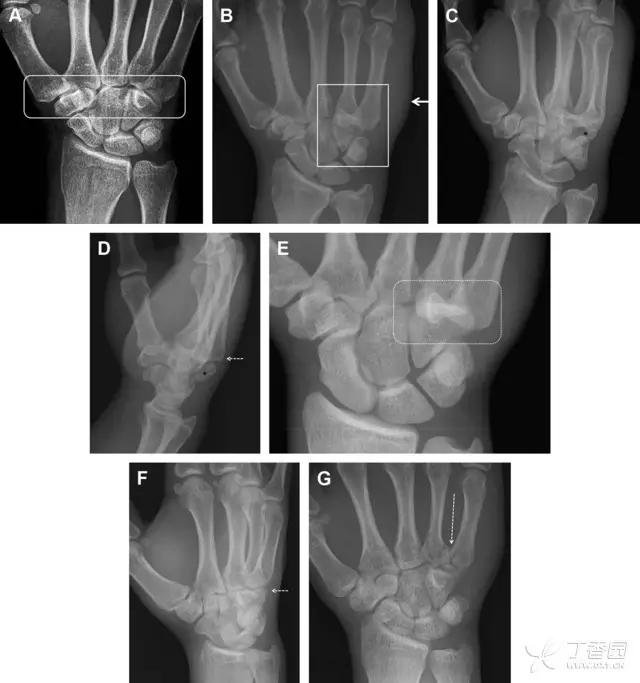

33 腕掌关节骨折脱位腕掌关节骨折脱位为高能量损伤,常伴有神经损伤。腕掌关节组成骨多,侧位片上重叠遮挡多,骨折不易发现,容易漏诊。在前后位片上,关节面不平滑、关节间隙不对称、关节皮质破坏、关节面重叠常提示腕掌关节骨折脱位。特别是第 4、5 腕掌关节脱位,在前后位片上不容易发现;该损伤不稳定,也称为「变异型拳击手损伤/骨折」。

图 4 第 4、5 腕掌关节骨折脱位。(A)正常腕掌关节,关节面平衡起伏、平行;前后位(B)、斜位(C)、侧位(D),第 5 掌骨近端附近软组织肿胀(白色箭头),冠状面关节面重叠,背侧撞击剪切应力致钩状骨骨折(*),在前后位及斜位片上可见双密度影。第 4 掌骨底部可见微小骨折碎片(D,虚线箭头),第 4、5 掌骨掌侧成角。(E~G)变异型拳击手损伤:第 4、5 掌骨背侧脱位而未见骨折(E,虚线方框),钩状骨有骨折小碎片(F,短虚线箭头),第 4 掌骨基底部关节内骨折(G,长虚线箭头)

34 钩状骨骨折

钩状骨骨折可发生于体部和钩部,钩部骨折更多见,可合并有第 4、5 腕掌关节脱位。受伤机制由直接*力暴**或腕横韧带撕脱伤所致。骨折征象包括钩部无显示、骨皮质边缘模糊、硬化或双密度影等。常规的正侧位常无法明确诊断,需要加拍腕管位,可清晰显示其钩部。

图 5 打高尔夫球后腕部急性疼痛。常规腕关节 X 线片正常(X)。腕管位片(B)隐约可见钩部横行骨折(虚线箭头),CT 检查(C、D)进一步明确了诊断

35 三角骨骨折

三角骨骨折是除舟状骨骨折外腕关节常见的骨折之一。其背侧是背侧桡腕韧带的附着点,因此背侧骨折更常见。常规正侧位片基本可明确诊断。背侧骨折可在侧位片上看到一小骨块。

图 6 三角骨骨折。(A)前后位片骨折不明显,(B)仅在侧位片上见一小骨块(短箭头),伴有软组织肿胀(长箭头)。